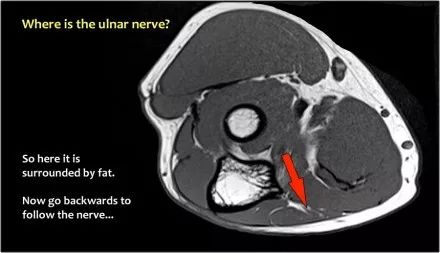

尺神经:在这里,我们看到了肘管内的尺神经。尺骨侧支带的后带形成隧道的底部,而支持带形成屋顶。

该患者有尺神经神经病变。肘管综合征是一种常见的周围神经病变。它产生于肘管内尺神经,其中该神经传递肘管支持带的下方的压缩。

因此,当我们回到图像时,您会发现很难找到神经。任何这些皮下结构都可以是转位神经。一种方法是远端跟随结构,直到你发现远端的尺神经位于由脂肪包围的前臂近端的正常位置。然后当你向近端跟随它时,你会发现这是皮下移位。

在这种情况下,有神经炎。神经增大。在T2W图像上有高信号。另一个标志是在矢状图像(箭头)上看到的束的不均匀扩大。